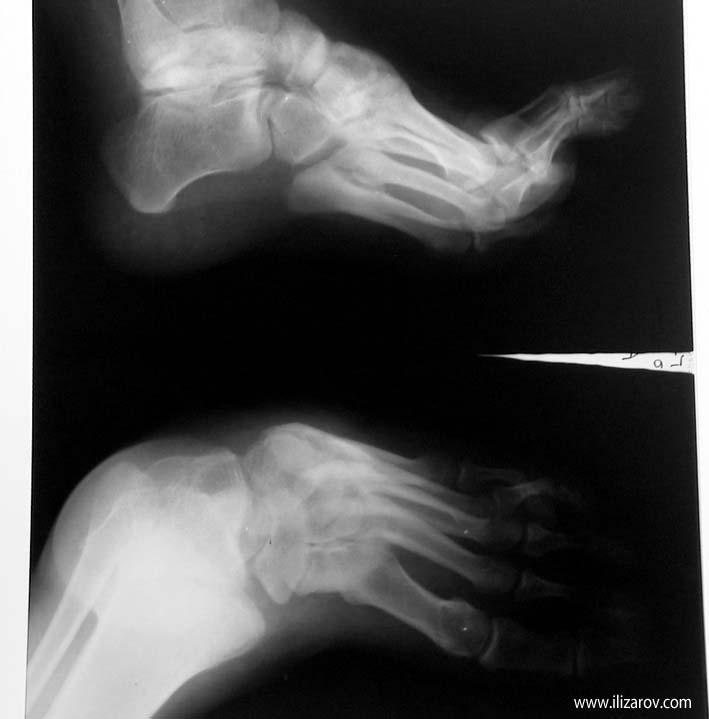

Case 2